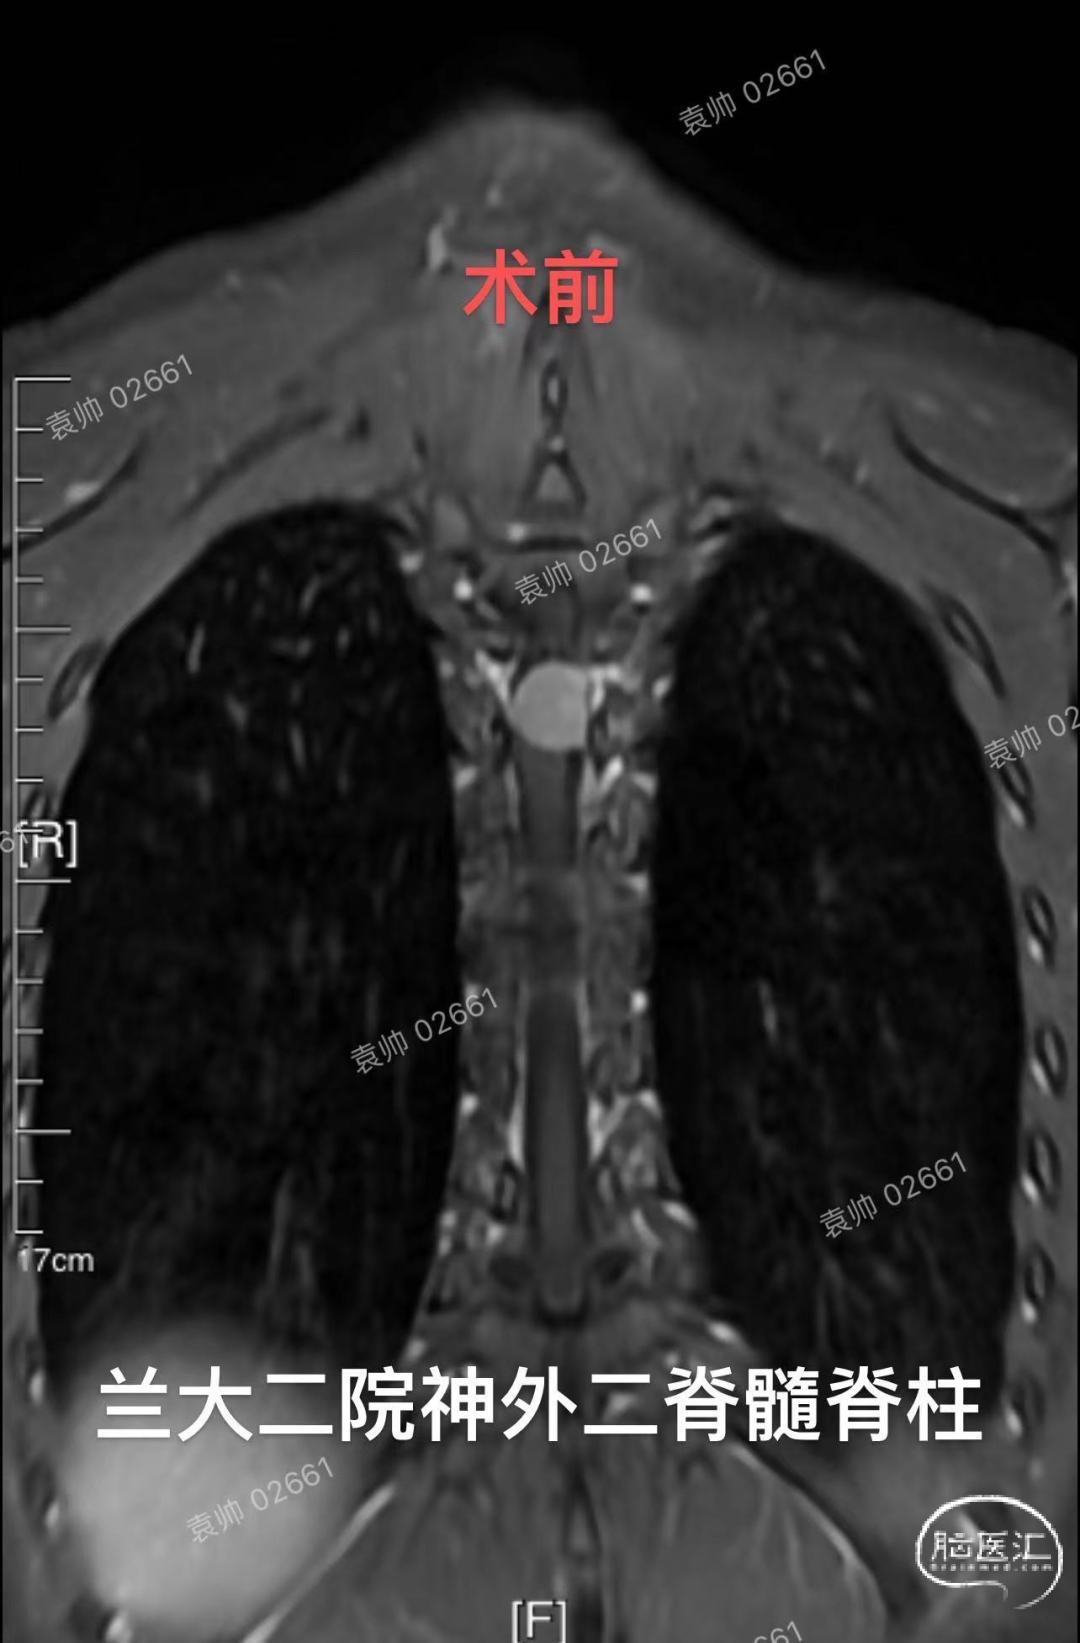

兰州大学第二医院神经外科二病区脊髓脊柱组病例分享:20岁年轻女性,T3-4脊髓背侧脊膜瘤。对于胸段脊膜瘤的治疗,大家都不陌生,手术难度不大,术后复发率低。但是相对于大多数凸面脑膜瘤,可以做到肿瘤基底硬膜全切,达到Simpson 1级切除,脊膜瘤全切附着硬脊膜,重建困难,容易术后脑脊液漏,并且对于年轻患者,不能完全避免肿瘤复发。由于硬脊膜内外层易于剥离,不同于硬脑膜,而脊膜瘤通常只会侵及内层硬膜,所以,我们推荐使用Saito技术,以剥除肿瘤附着硬脊膜内层,达到近似Simpson 1级切除的效果,可以有效预防肿瘤复发。